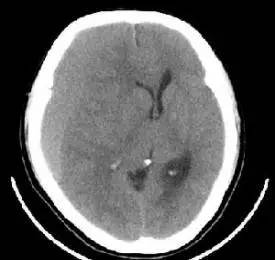

慢性硬膜下血肿CT图片

硬膜下血肿:呈新月形. 急性硬膜下血肿在脑表面呈新月形或半月形高密度区。而慢性硬膜下血肿在颅骨内板下可见一新月形、半月形混杂密度或等密度阴影,中线移位、脑室受压。

急性硬膜下血肿在脑表面呈新月形或半月形高密度区。而慢性硬膜下血肿在颅骨内板下可见一新月形、半月形混杂密度或等密度阴影,中线移位、脑室受压。